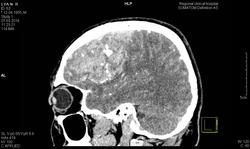

сделали КТ г/м с контрастным усилением для верификации диагноза. закл. кт-картина длительно существующего сосудистого образования в правой лобно-теменной области (АВМ) (не исключается и объемный процесс), осложненного кровоизлиянием, с выраженным сдавлением боковых и III желудочков и латеральной дислокацией до 14 мм. Эпи-, субдуральная гематома в правой лобно-теменной области. Отек головного мозга. Такое ощущение что там нет АВМ!!!!!!!!!!!!

Окно в jpeg неудачное. Нечто с кровоизлиянием, согласна. Остальное - после dicom.

Нейрохирурги посмотрели сказали, что КТ картина точно подходит под АВМ с характерным распространение кровоизлияния. И тактически не стоит делать декомпрессионную трепанацию - велик риск массивного кровотечения. Была бы опухоль..., тогда можно трепанацию и т.д.

Треба дайкомы. На АВМ очень похоже. Пропуск сосудистой мальформации грозит сюрпризом для хирургов в качестве массивного кровотечения. Вот задумайтесь над этим.